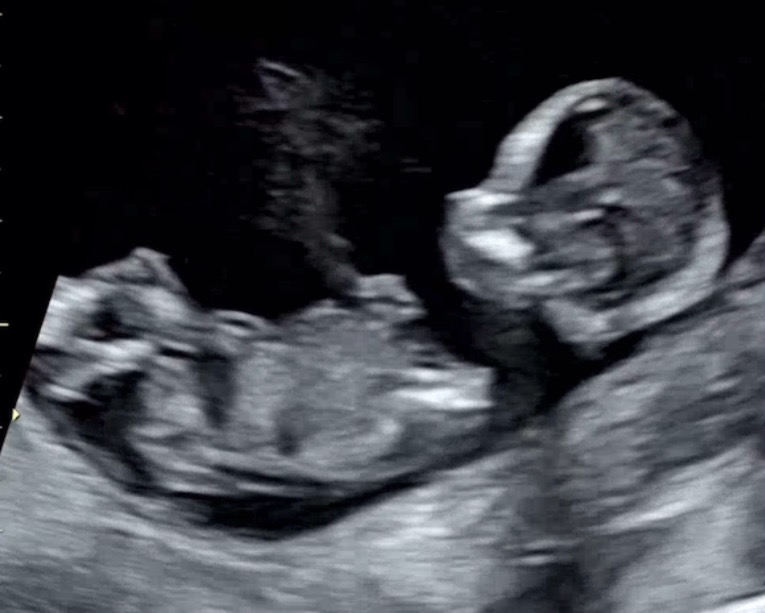

딸일까요? 아들일까요?

12주 4일차에 정밀초음파 보고 왔습니다. 검사중에 콩떡이가 너무 활발히 움직여서 목투명대랑 콧뼈도 간신히 보고 왔네요^^ 오늘 본 초음차 사진인데 각도법으로 성별 알수 있을까요? 너무너무 궁금하네요~